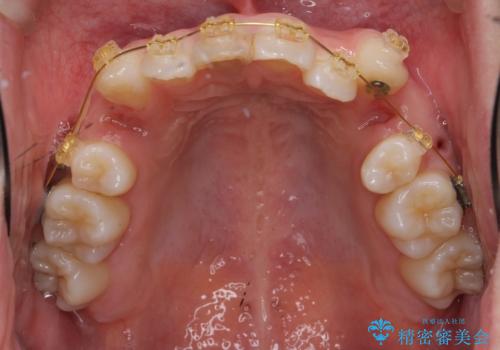

- 審美装置

上下左右の小臼歯を抜歯し、ワイヤー矯正を行いました。

犬歯のコントロールが難しく、矯正用ミニスクリューを併用しました。

奥歯の歯の間が狭く、ミニスクリューを入れるのも難しい症例でした。